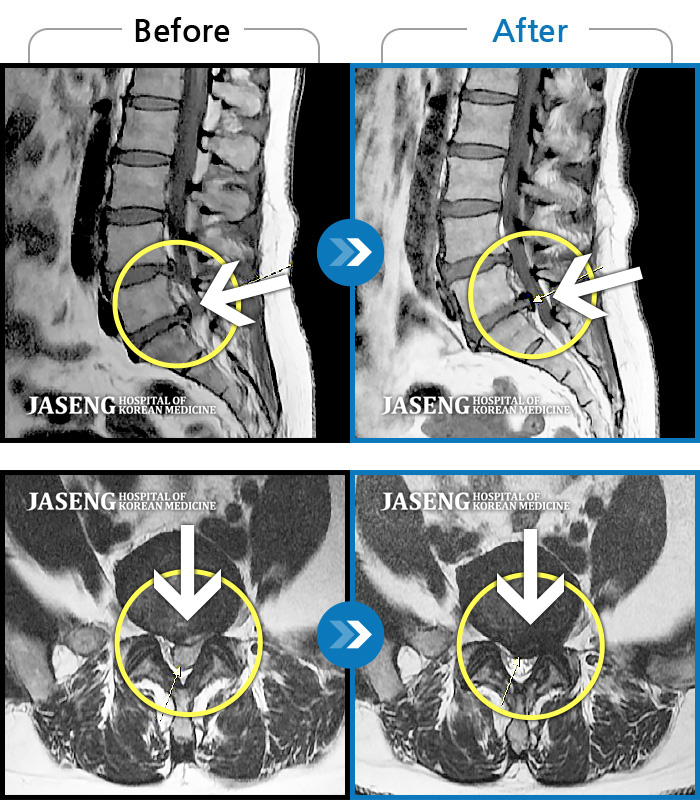

ȯںп Ǹ ǿ ԿǾ, ο ġ ۿ Ƿ ġḦ Ͻñ ٶϴ.